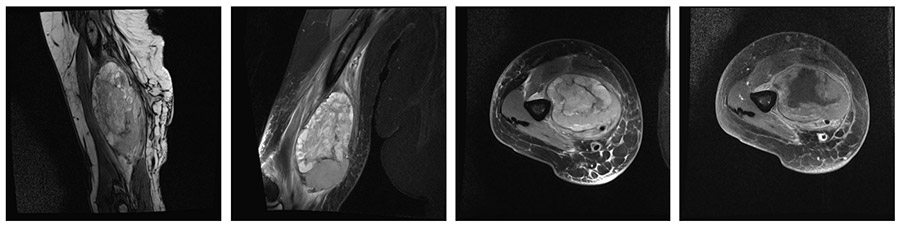

Ameliyat Öncesi: MR’da kol medialde humerus üzerine oturmuş nörovasküler yapıları itmiş düzensiz sınırlı heterojen kitle görülmekte